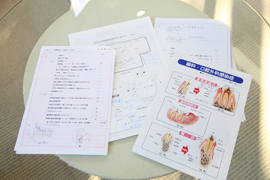

「親知らず」ってどういうときに抜くの |

|

| 次回の口腔外科のオペの日は |

|

|

ゴールデンウイークの関係上、 5月16日(金曜日)を予定しております |

![]() 親知らずの抜歯などの口腔外科

親知らずの抜歯などの口腔外科